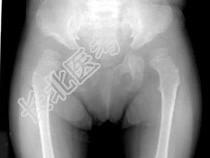

- 单项选择题女,3岁, 身高不增,智力正常, 结合图像,最可能的诊断是 ( )

C、黏多糖贮积症Ⅳ型